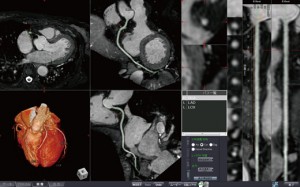

○MR冠動脈解析2(図1)